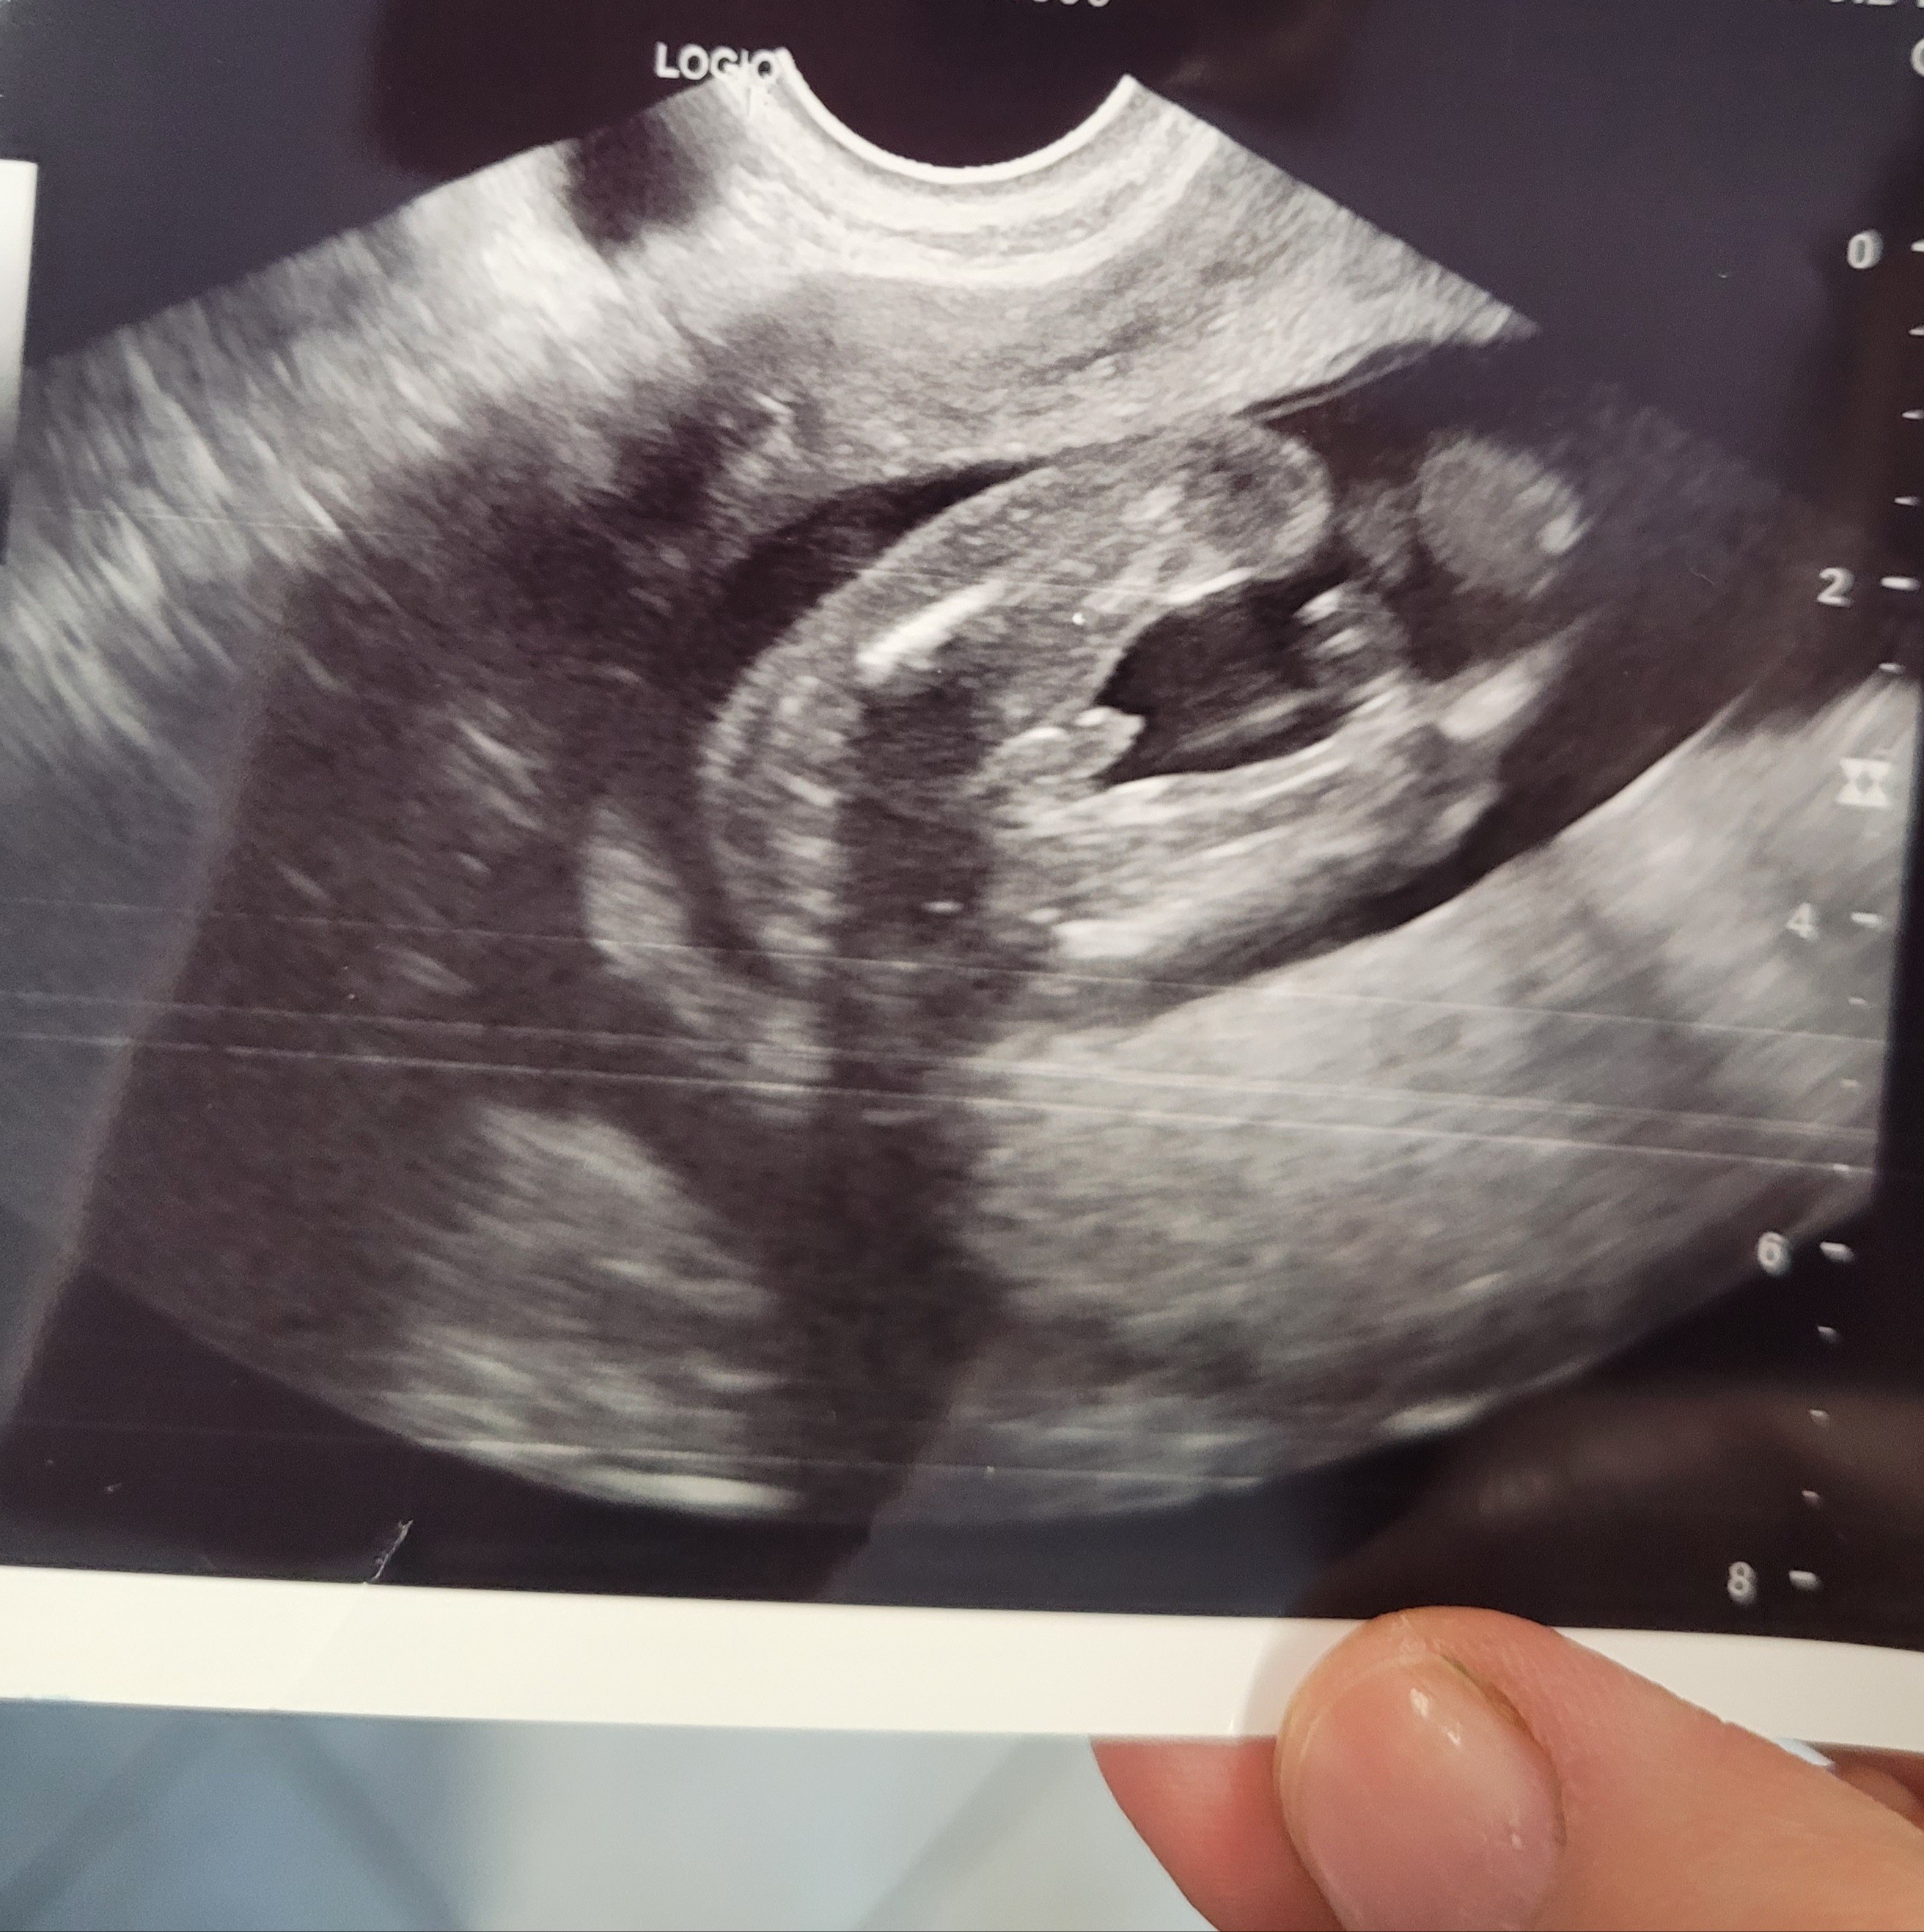

Witam Was Dziewczyny. Powiedzcie swoim okiem co widzicie. Chłopca? Czy dziewczynkę? Usg robione w 16 tygodniu. Dziecko jest wypięte pupa i ma zgięte nóżki. Może mieliście podobne zdjęcia i jesteście w stanie podzielić się swoimi doświadczeniami

Nie była pewna, na 70 procent chlopczyk dlatego pytam bo istnieją pomyłki.

Pomyłki istnieją i pewnosci miec nie mozesz do samego porodu:) u corki miedzy nozkami nie dzialo sie tak duzo, byla typowa "buleczka" z kreskami, u synka wlasnie tak jak u Ciebie wystawal siusiak. Mysle ze na kolejnej wizycie lekarka da Ci troszke wiecej niz 70%, w jedna lub w drugą strone:) lub dziecko bedzie sie ukrywac i zostanie wyprawka neutralna:p

Właśnie dlatego dodałam ten post bo jestem ciekawa waszych doswiadczeń;) wiem ze pomyłki się zdarzają i nie kiedy ptaszki okazują się bułeczkami ponieważ lechtaczka jest spuchnieta lub dziecko ma pępowinę między nóżkami:) czekam na opinie innych mam :) Pozdrawiam Cie Cieplutko 🥰